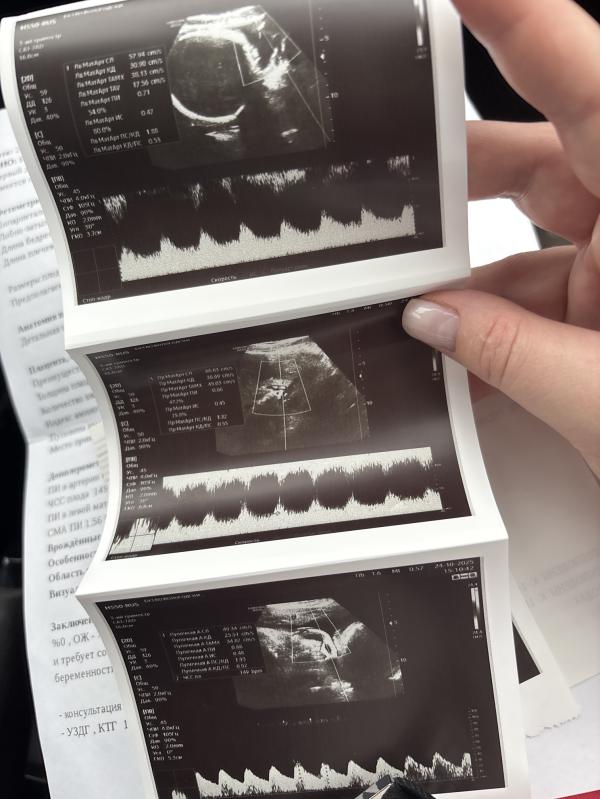

А третий скрининг был ?)🙋🏼♀️🤰🏼